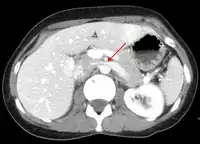

The nutcracker syndrome results from compression of the left renal vein between the aorta and the superior mesenteric artery.

The nutcracker syndrome (NCS) results most commonly from the compression of the left renal vein (LRV) between the abdominal aorta (AA) and superior mesenteric artery (SMA), although other variants exist.[1][2] The name derives from the fact that, in the sagittal plane and/or transverse plane, the SMA and AA (with some imagination) appear to be a nutcracker crushing a nut (the renal vein).